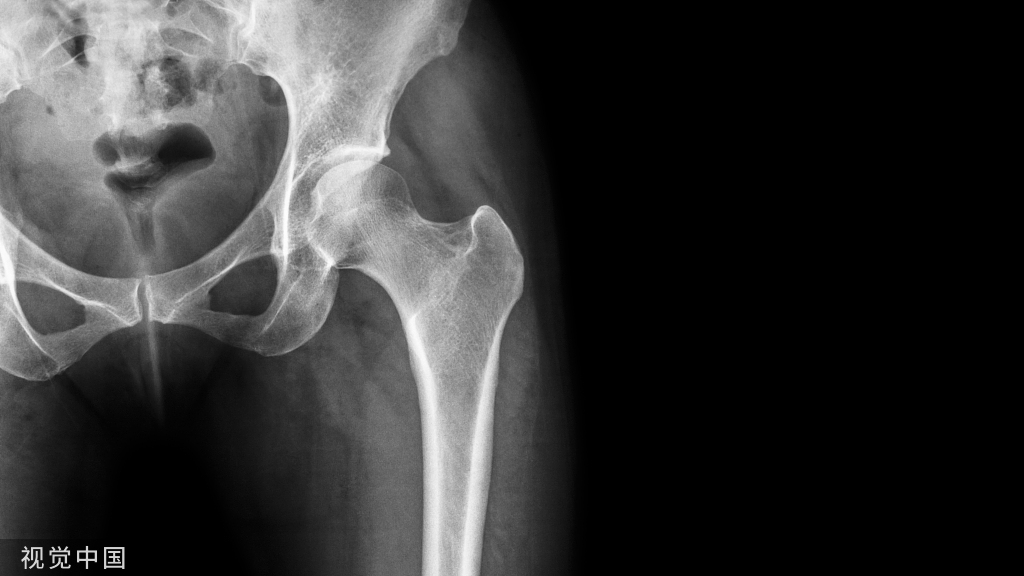

慢性根尖周脓肿(CAA chronic apical abscess)慢性根尖周脓肿(图10和11)是由长期持续的炎症引起的。脓液穿通骨和口腔黏膜,并通过口腔黏膜或上皮的瘘管流出。这些通到表皮的瘘管通常可能作为皮肤损伤而被错误处置。此外,瘘管也可能存在于牙周并通过龈沟引流。瘘管可以部分或完全地被上皮所包绕,这些上皮又被炎性结缔组织包围。临床诊断显示牙髓电活力测试结果为阴性。除非瘘管闭合,否则叩诊和触诊通常都不会引起疼痛。放射学检查,根尖周组织表现从无变化到发生明显变化。

图10:17 牙齿CAA。术前放射学检查,利用牙胶尖显示瘘管。患者因17 牙齿局部瘘管而前来就诊,诉无特殊临床症状。